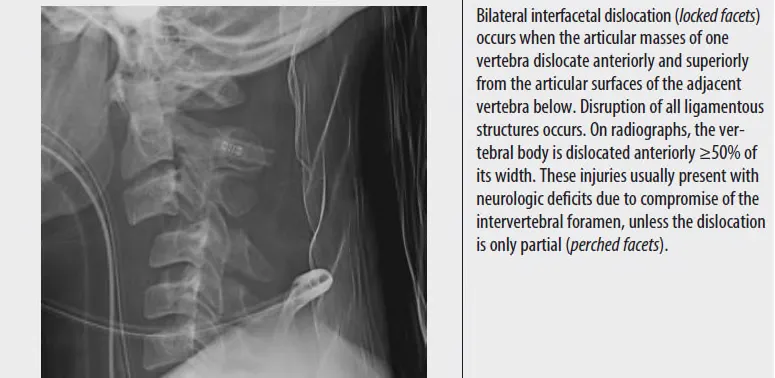

③ Bilateral interfacetal dislocation (Unstable)

⑤ Bilateral interfacetal Dislocation (unstable)

: Hyperflexion에 의해 발생하며 모든 인대의 disruption이 동반되고, 주로 신경학적 증상이 동반됨.

: Lat. view에서 vertebral body가 폭의 50% 이상 앞으로 전위되어 있다.